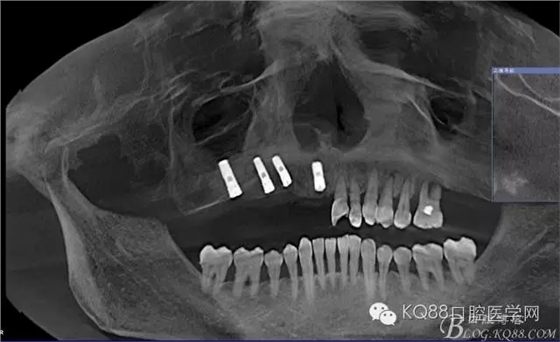

輔助檢查:ct示骨密度良好,11 12區(qū)域骨下有一水平向埋伏牙,15 16區(qū)域骨高度2.5-3mm,骨寬度6-9mm。

治療計劃:11 12 13及埋伏牙拔除,同期上頜竇外提升手術(shù)及種植修復(fù)